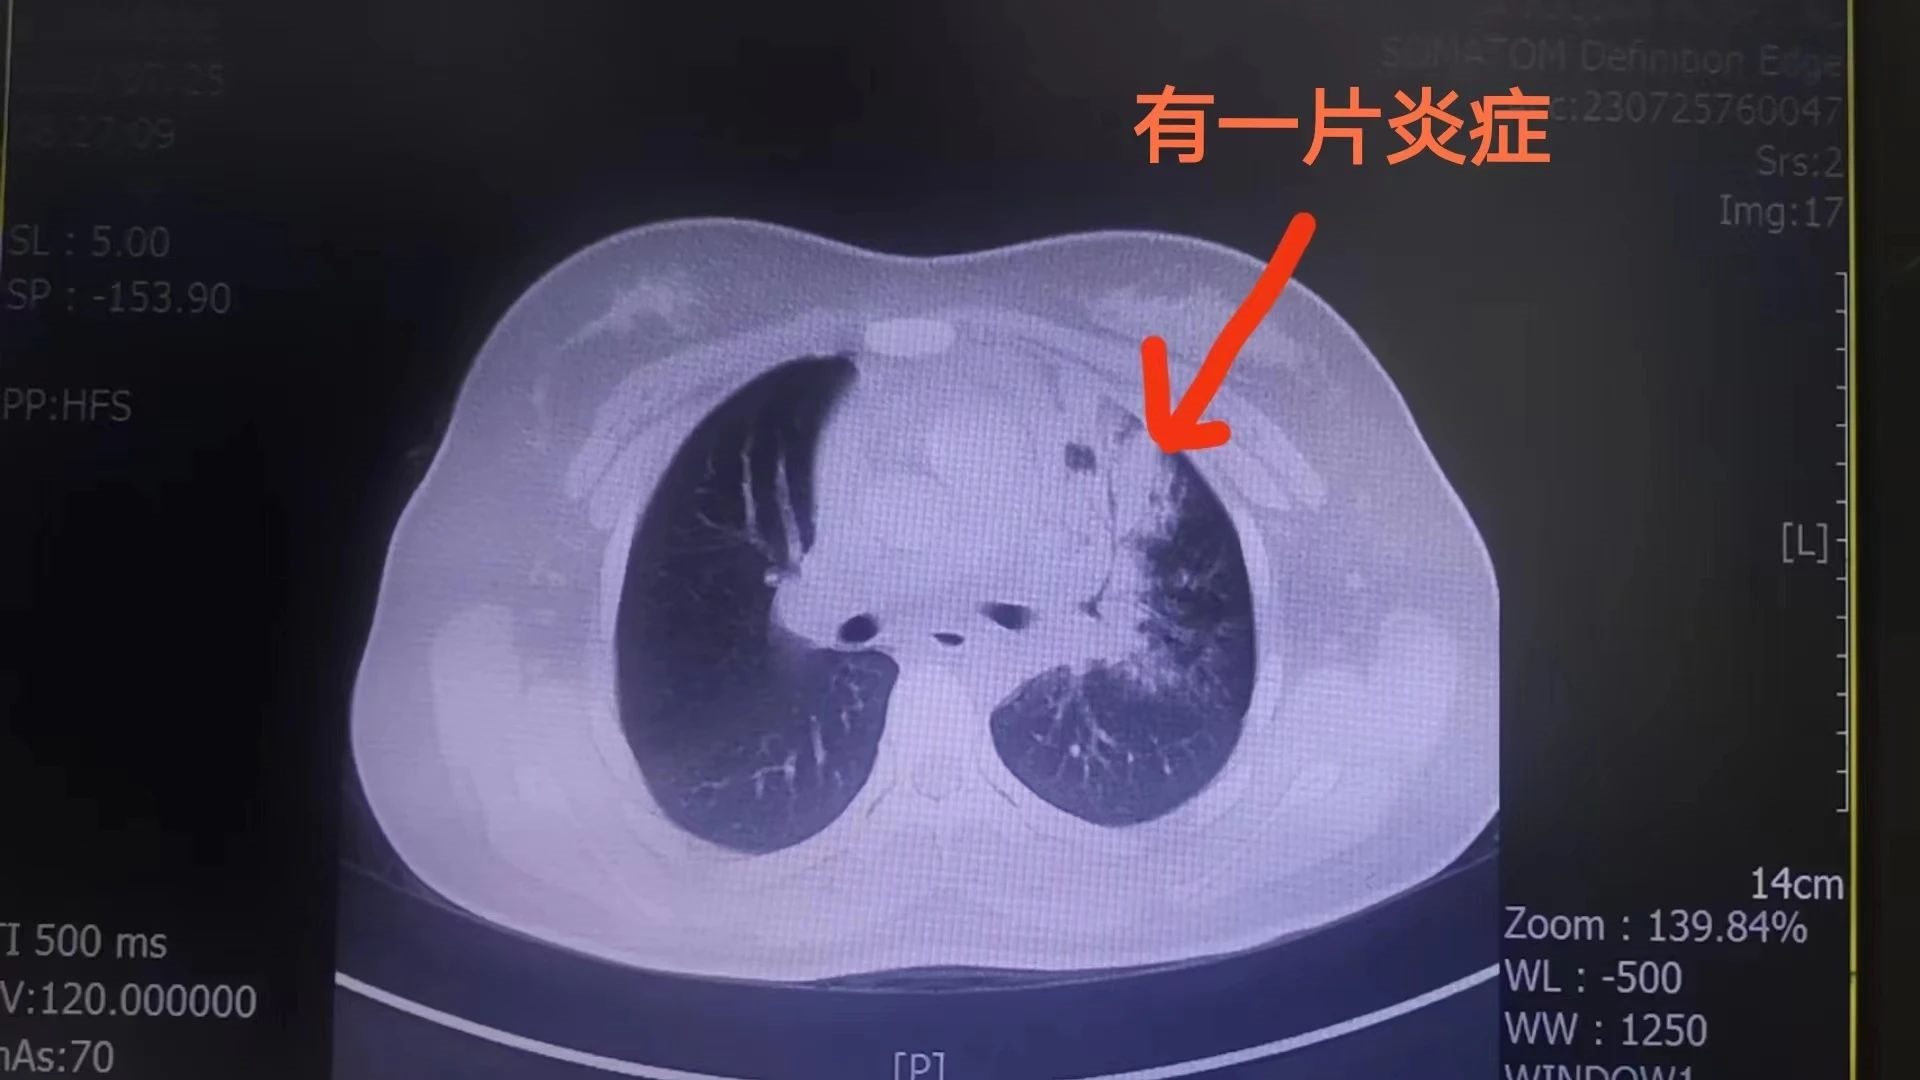

該患兒因“反復(fù)咳嗽1個(gè)月”在當(dāng)?shù)匦l(wèi)生院多次治療后無明顯好轉(zhuǎn),遂就診于我院兒科門診,行肺部CT提示大葉性肺炎、肺不張,兒科主任吳清泉主任醫(yī)師立即將患兒收治入院,并邀請(qǐng)泉州市兒童醫(yī)院呼吸科鄭敬陽教授對(duì)患兒進(jìn)行會(huì)診。鄭教授在充分了解患兒病情并為其檢查后,建議行纖支鏡探查。在征得家屬同意后,兒科傅祥彬主治醫(yī)師在鄭教授的指導(dǎo)下對(duì)患者實(shí)施局麻下支氣管鏡檢查和鏡下肺泡灌洗術(shù),術(shù)中清理了氣管和肺內(nèi)大量的膿性分泌物,手術(shù)歷時(shí)20分鐘順利完成。術(shù)后,患兒生命體征平穩(wěn),在父母及護(hù)士的陪同下安返病房。

術(shù)前、術(shù)后CT對(duì)比